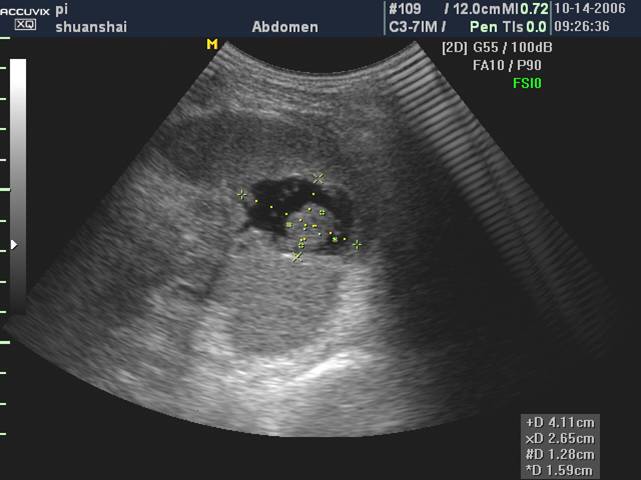

包膜下脾破裂(脾包膜下血肿)

脾包膜下血肿常伴有包膜一表浅部位的脾实质挫裂伤。

声像表现:该处包膜隆起,呈弧形凸出,包膜下为梭形无回声或低回声区。血肿内可有低回声团块和沉淀物,也可有条索状分隔样结构。